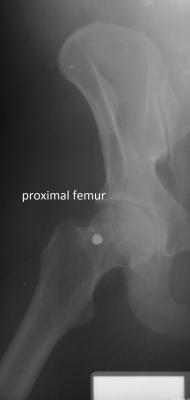

The researchers compared ante-mortem and post-mortem lateral craniofacial (side of the skull) X-rays for 20 individuals, and did the same for X-rays of the vertebral column (spine) for 50 individuals and X-rays of the proximal femur (upper leg) for 23 individuals. The researchers used these evaluations to develop location-specific standards for each skeletal region. The researchers focused on these skeletal regions because they are among the most frequently X-rayed in a clinical setting.